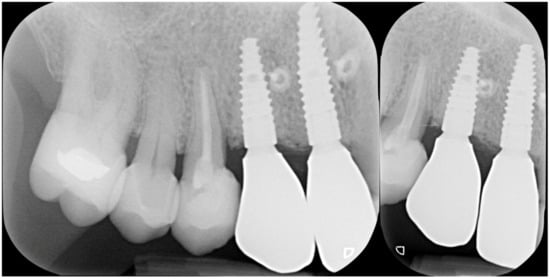

Figure 4.

Rx taken at a 5 year follow-up showing the stability of the regeneration on both implant and tooth side.

Three months after implant surgery the fixture was restored with a ceramic crown and a radiograph taken 5 years after augmentation. Figure 4 not only shows the perfect maintenance of the osseointegration after loading, but also how the GTR effect is visible on the mesial of tooth 26 with an attachment gain of 6 mm; the probing (PPD) at the time of recall was 3 mm The tooth remained in function and the patient can clean the area well with interproximal tooth brushes and dental floss.